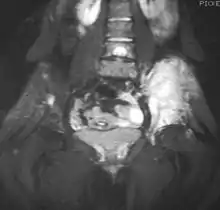

Magnetic resonance imaging (MRI) should be routinely used in the work-up of malignant tumors. It will show the full bony and soft tissue extent and relate the tumor to other nearby anatomic structures (e.g. vessels). Gadolinium contrast is not necessary as it does not give additional information over noncontrast studies, though some current researchers argue that dynamic, contrast-enhanced MRI may help determine the amount of necrosis within the tumor, thus help in determining response to treatment prior to surgery.[27]

Computed axial tomography (CT) can also be used to define the extraosseous extent of the tumor, especially in the skull, spine, ribs, and pelvis. Both CT and MRI can be used to follow response to radiation and/or chemotherapy. Bone scintigraphy can also be used to follow tumor response to therapy.[28]